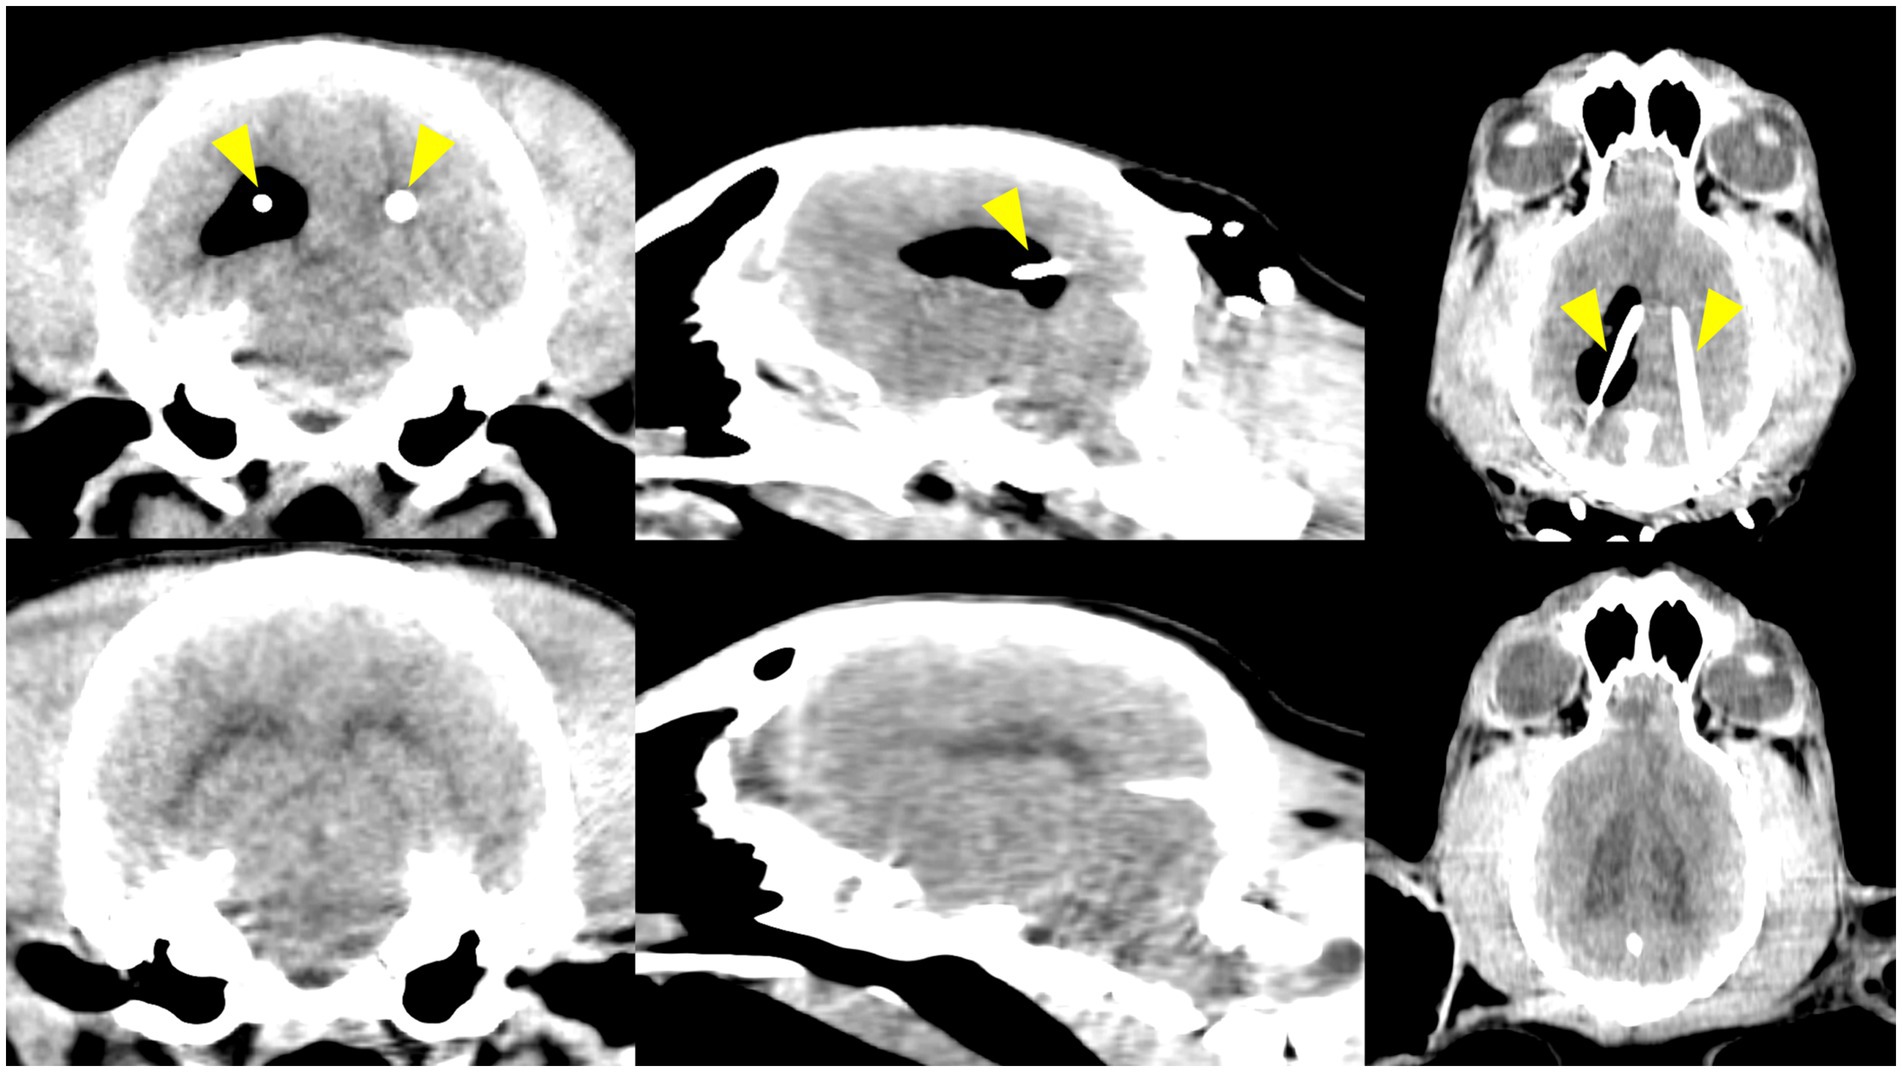

Background: Ventriculoperitoneal shunting (VPS) is an effective treatment for canine hydrocephalus, but complications related to ventricular catheter (VC) misplacement remain a concern. Although neuronavigation improves accuracy, its cost and complexity limit veterinary use. Patient-specific 3D-printed guiding systems (PS-3DGS) offer a potential alternative. Objectives: To compare the accuracy and feasibility of PS-3DGS compared to electromagnetic neuronavigation for VC placement in 3D-printed canine cranio-ventricular models (CVMs) and Beagle dogs. Animals and study design: Ten 3D-printed CVMs (ex vivo study) and five experimental Beagle dogs (in vivo study). Methods: VC placement was performed using PS-3DGS and neuronavigation in CVMs and experimental animals. Accuracy was assessed by the distance from the VC tip to the foramen of Monro (DFM), tip coordinates (X, Y, Z axes), tip placement error, intraventricular insertion length (IIL), and catheter contact with the ventricular wall (VVL). Intraoperative procedural time and anatomical variables, including skull and cranial indices, were also analyzed. Results: PS-3DGS showed no significant difference in DFM compared to neuronavigation in CVMs and Beagle dogs. PS-3DGS achieved significantly lower VVL and reduced procedural time than neuronavigation in the CVM study (p=0.011 and p=0.039, respectively). In dogs, DFM with PS-3DGS was comparable to both neuronavigation and the ex vivo results. Entry point error correlated negatively with cranial index (r=-0.9, p=0.037). Conclusion: PS-3DGS provided accuracy comparable to neuronavigation while simplifying the procedure. It represents a viable, cost-effective alternative for canine VPS surgery, potentially enhancing catheter placement and reducing complications.